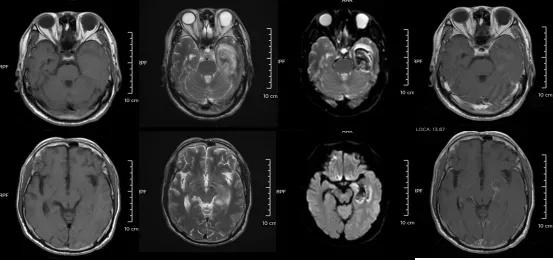

某单纯疱疹病毒性脑炎患者的医学影像。图源:浙江大学医学院附属第二医院

但如果拖延治疗,甚至会引发脑炎,可能出现癫痫、肢体偏瘫、尿潴留、认知功能障碍等严重后遗症,恢复时间长达3-6个月,甚至影响终身。